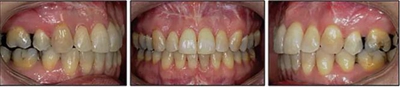

患者曾行正畸治療,現(xiàn)覺(jué)笑容不美觀前來(lái)就診。患者正面觀及側(cè)貌示下頜發(fā)育不足,偏高角,唇閉合不全。上下頜中線齊。覆合、覆蓋4毫米。磨牙關(guān)系及尖牙關(guān)系II類(lèi)。上頜擁擠度4mm,下頜擁擠度6mm。4顆第一前磨牙在第一次正畸治療時(shí)已拔除。上下牙弓呈尖圓型,牙弓狹窄。

患者側(cè)貌改善,下唇唇肌緊張消失,上下唇可自然閉合。磨牙及尖牙關(guān)系糾正至I類(lèi),覆合覆蓋正常。上下頜弓型糾正至卵圓形,牙弓寬度增加。頭影測(cè)量分析示SNA角81.8°,ANB角3°。頭影測(cè)量重疊圖示下頜骨向后旋轉(zhuǎn),垂直面高度略有增加。